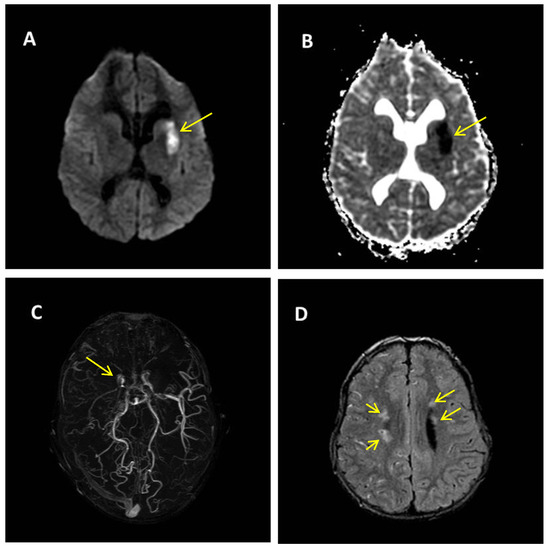

Figure 2.

Brain magnetic resonance imaging (MRI) at the age of 10 years, after the first TI sequence. (A,B) Diffusion weighted imaging (A) and diffusion coefficient map (B) show a lesion of the left lenticular nucleus of the anterior part of the internal capsula, and the head and body of the lateral nucleus caudatus characterised by reduced diffusion due to an acute ischemic lesion (yellow arrows). (C) Angio-TOF MRI showing the stenosis of the right carotid siphon apex (yellow arrow) associated with poorly visualised flow of the ipsilateral middle cerebral artery, stenosis of the left carotid siphon apex, and a stretch of the M1 ipsilateral middle cerebral artery; (D) Fluid attenuation inversion recovery (FLAIR) sequence: small areas of signal hyperintensity at the semioval centres bilaterally (yellow arrows), most marked on the right side.

One year later, during a febrile episode, he experienced a tonic-clonic seizure involving the right upper limb. He repeated brain MRI associated with cerebral angiography, which failed to visualise the right internal carotid artery but showed a severe stenosis of the left internal carotid artery in association with dilated collateral middle cerebral artery (MCA) vessels having the typical “puff of smoke” aspect (Figure 2C). A CT scan with acetazolamide showed a marked reduction in the time of transit of the contrast medium in bi-hemispheric cortical space that suggested reduced perfusion in both the Sylvian and the anterior circulation territories of the carotids bilaterally, with no signs of reserve. On the basis of the established criteria [23], the neuroradiological findings were diagnostic of MA.